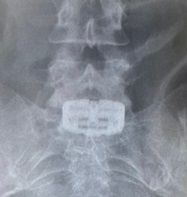

전방 경유 척추 유합술용 높이확장형 케이지 '패스락-TA'를 삽입한 첫 수술 사진. (사진=엘앤케이바이오). *재판매 및 DB 금지

[서울=뉴시스] 김경택 기자 = 척추 임플란트 전문기업 엘앤케이바이오메드는 전방 경유 척추 유합술용 높이확장형 케이지 '패스락-TA'로 미국에서 첫 수술을 성공적으로 마쳤다고 25일 밝혔다.